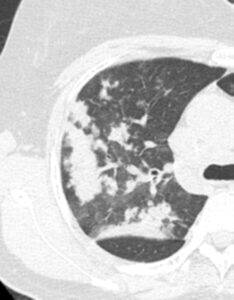

(実際の症例 乾酪性肺炎 51歳女性)

胸部CT

大きな白い影の周囲に、小さな白い粒々と、そこから枝分かれするような細い線が多数見られます。

これは、木の枝が芽吹いている様子に似ていることから**「Tree-in-bud appearance樹枝状影」**と呼ばれます。

これは、結核菌などが細気管支(気管支の末端)に詰まり、そこで炎症を起こして肥厚している状態を反映しています。